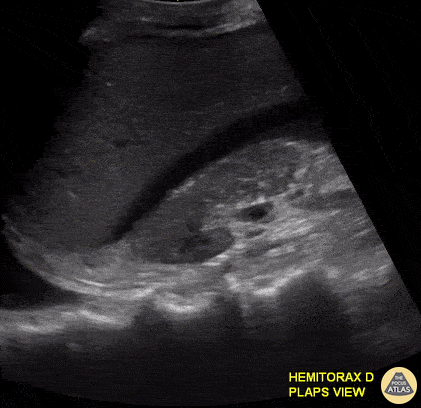

This 30-year-old male was brought to our ED after a fall from scaffolding with evidence of trauma to his right thoracoabdominal region. E-FAST performed in the RUQ revealed both the presence of free fluid within Morrison's pouch and an ipsilateral hemothorax. Appreciate the presence of “spine sign” as an additional ultrasonographic indicator of free fluid within the pleural space. Renato Tambelli, Emergency Physician Hospital das Clínicas de Marília, Brazil. @R_Tambelli // @JediPocus